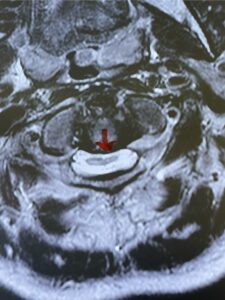

This is a 59 year-old female with a history of cerebral palsy and a prior C3-C7 posterior cervical laminectomy and instrumented fusion two years prior. She did ok until she developed progressive weakness of all four extremities and numbness. Imaging revealed she had a significant breakdown above the fusion at C2-3 with a grade 2-3 spondylolisthesis of C2 on C3 with severe spinal cord compression (Fig. 9). It was surprising the degree of anterior fusion induced by the posterior fusion from C 3-C 7 (Fig. 10). Because of her progressive neurological dysfunction in a patient who was already compromised because of her cerebral palsy, it was clearly necessary to decompress from occiput to C 3. We utilized her prior lateral mass screws although we removed bilaterally the C7 screws to reduce the fulcrum-effect on the C7-T1 junction as the C 6-7 level was solidly fused. We performed an occiput to C 6 fusion with occiput to C3 laminectomy (Fig. 11) Post operatively we had good placement and alignment (Fig. 12) The patient went to rehab with improvement of strength and numbness particularly in hands.

Fig. 9: Sagittal T2-weighted cervical MRI demonstrating severe upper cervical spinal cord compression secondary to C2 anterior subluxation on C3 with development of thickened posterior degenerative material (red arrow).